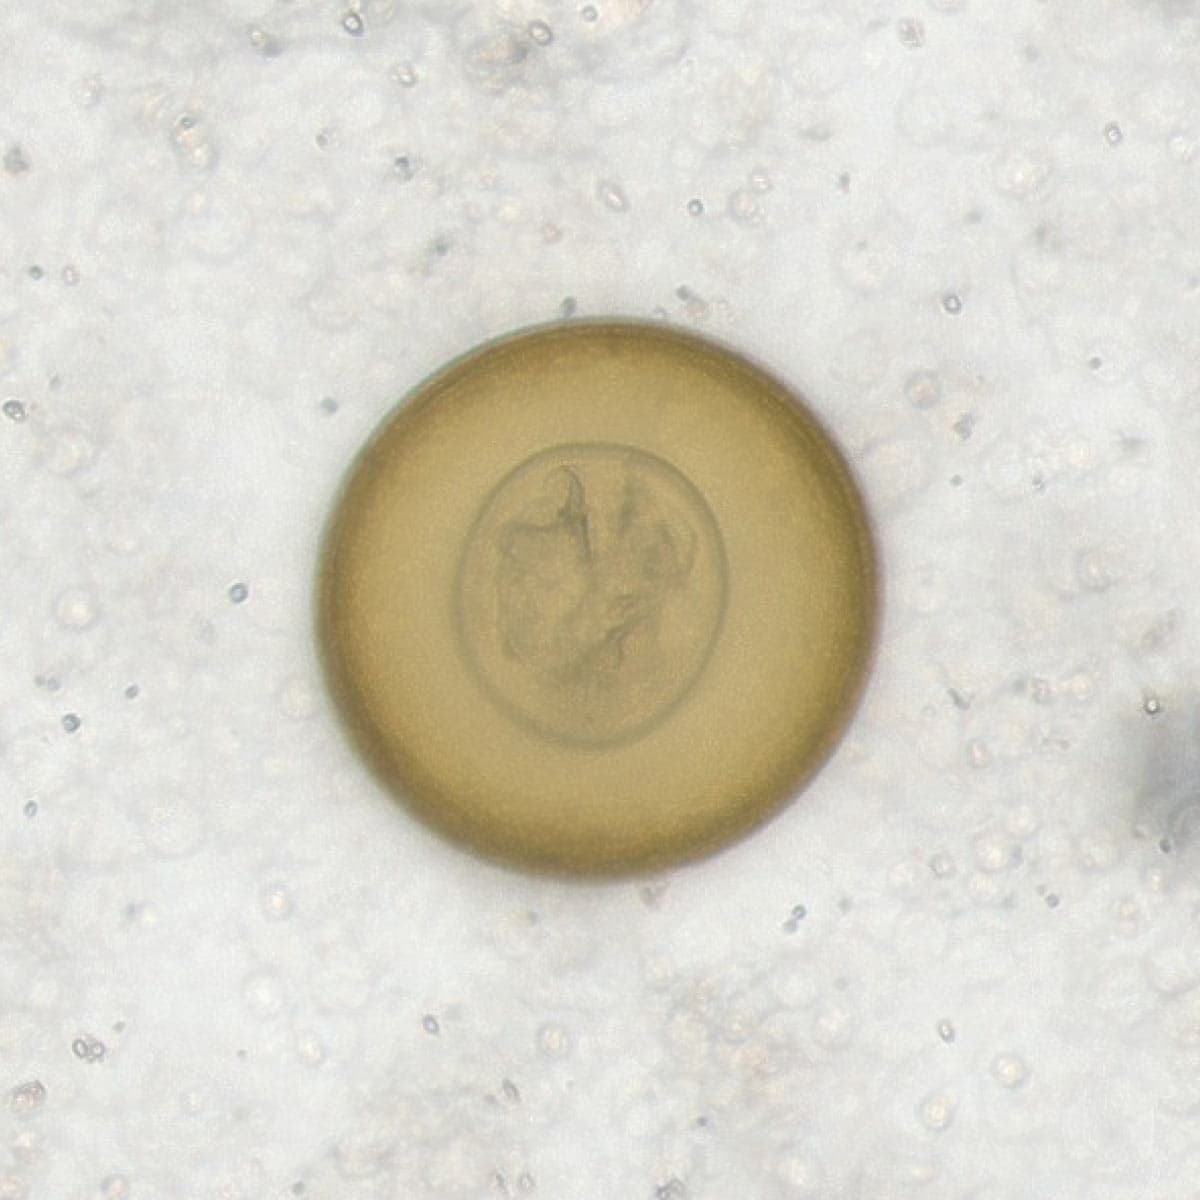

Automatic detection of rare species

Built on worldwide parasite-positive specimens, ParaScout AI identifies a vast number of parasite species, including those that are clinically rare or challenging to find.